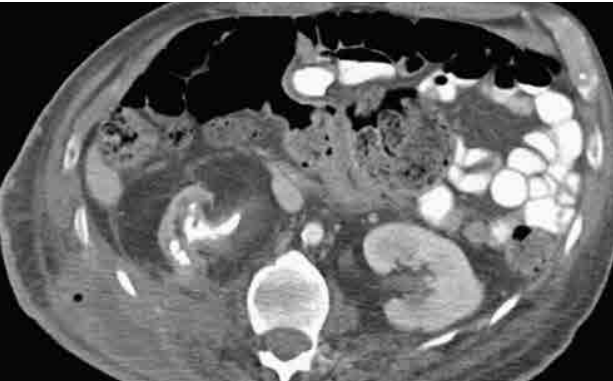

Mulher de setenta anos de idade, obesa, portadora de diabetes mellitus e histórico de nefrolitíase dá entrada no pronto-socorro com dor lombar à direita há três dias, febre aferida, diminuição da diurese e mantendo estabilidade hemodinâmica. Foram realizados exames laboratoriais, que evidenciariam o aumento de provas inflamatórias, escórias nitrogenadas e urina tipo 1 infecciosa. Também foi realizada tomografia de abdome e pelve, com contraste endovenoso.

Com base nesse caso hipotético e considerando a avaliação do corte tomográfico na imagem acima e a hipótese diagnóstica, a conduta correta na urgência será

Com base nesse caso hipotético e considerando a avaliação do corte tomográfico na imagem acima, a principal hipótese diagnóstica é